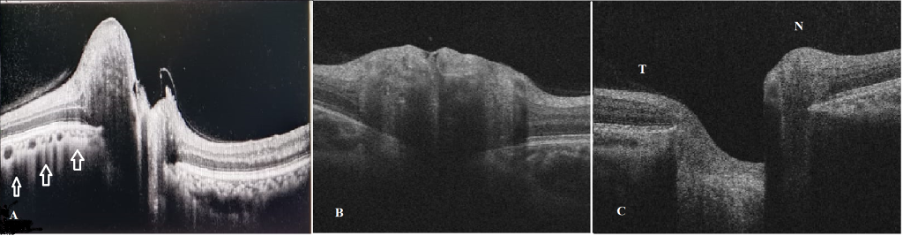

C.Qualitative analysis

Transverse OCT scan through the optic nerve head can help us understand the morphology of the disc with respect to the Bruch’s membrane layer. Increase in intracranial pressure will lead to anterior bowing of the Bruch’s membrane layer, which has a V-shaped or flat configuration in normal population. The morphologies described in papilledema are W, S, and dome-shaped.[5] EDI-OCT (enhanced depth imaging OCT) has been found to have the highest sensitivity to detect optic disc drusen. It is seen as a hyporeflective mass with hyper-reflective borders suggestive of a buried disc drusen.

In a myopic oblique insertion of disc (MOID), that is commonly seen in myopes, the disc is inserted in a way that the nasal margin of the disc is elevated and the temporal margin is flat. This may simulate early papilledema. In eyes with high hypermetropia (>5D), the disc is usually smaller, crowded, and has minimal cupping and thus, may simulate papilledema. OCT RNFL parameters are within normal limits and thus helps to differentiate it from papilledema.[7]

Another important qualitative feature of OCT in identifying papilledema from ODD is the presence of retinal and retino-choroidal folds and creases. They are seen on fundus imaging, and better visualized on enface OCT and include circumpapillary folds, inner retinal folds, outer retinal folds, and choroidal folds. [6] These might be seen in optic disc drusen as well.